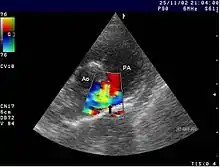

Se pueden observar cambios en radiografías del tórax. El diagnóstico se confirma con una ecocardiografía.